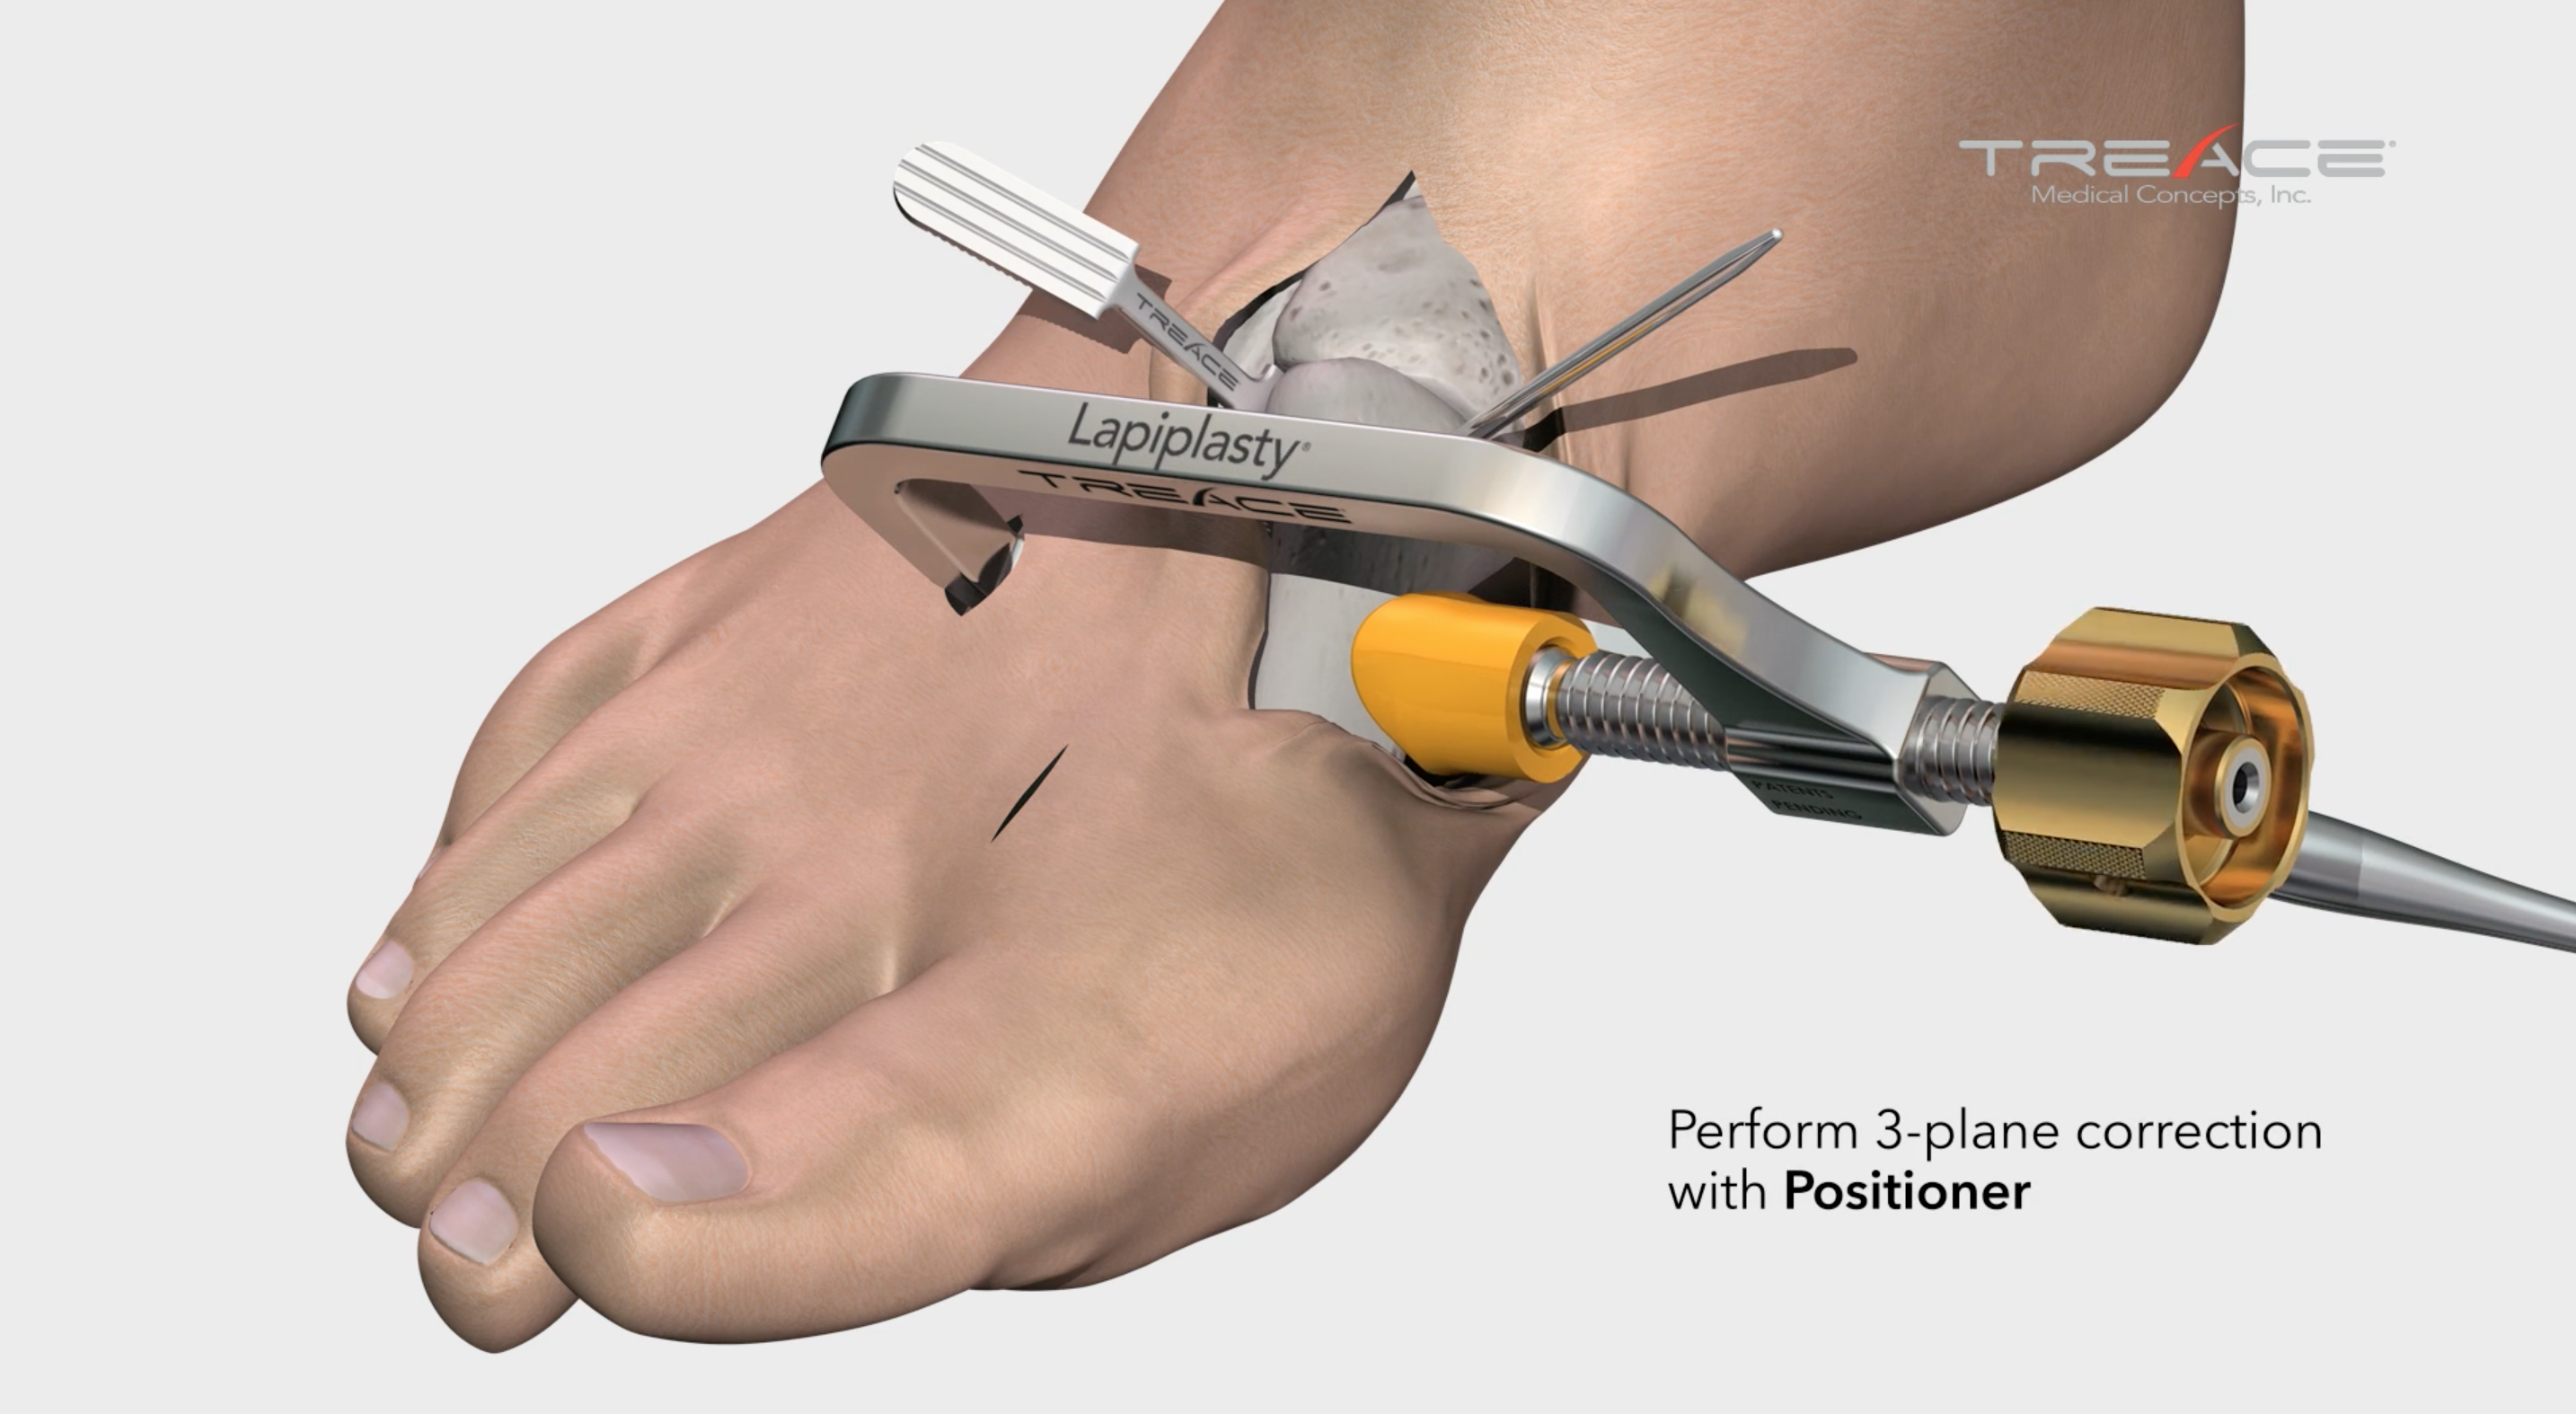

1. Correct

Make Your Correction Before You Cut

The Lapiplasty® Positioner is engineered to quickly and reproducibly correct the alignment in all three planes, establishing and holding true anatomic alignment of the metatarsal and sesamoids.1